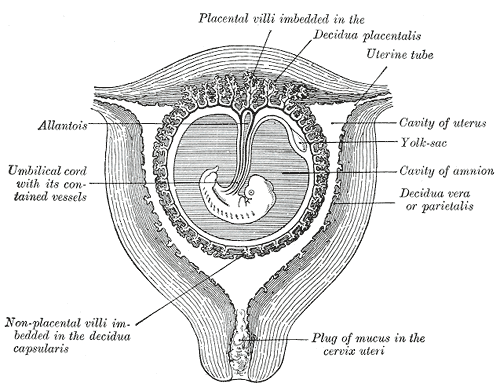

Амнион и Околоплодные Воды: Функции и Роль в Беременности